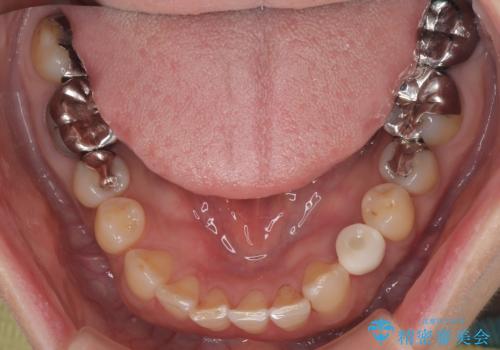

診査の結果、左下に残存していた乳犬歯が水平的に破折しており、残念ながら保存は困難な状態でした。

また、右下にはスペースがあり、左上にも乳犬歯が残存しているという状態で、治療方法としては矯正治療を含めた複数の選択肢が考えられました。